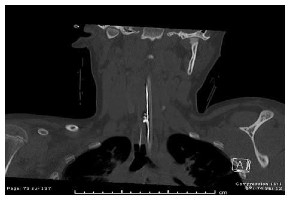

Fracture de Jefferson au niveau de l’arc antérieur C1 (première vertèbre) et élargissement du canal rachidien secondaire à la fracture de l’arc antérieur de C1.

Les radiographies peuvent détecter plusieurs fractures cervicales, telle que la fracture de Jefferson au niveau de la deuxième vertèbre. Ce type de fracture crée une ouverture de l’anneau de la première vertèbre et, en conséquence, un élargissement du canal rachidien (conduit à l’intérieur de la moelle épinière). Il est possible de voir une entorse grave des deux premières vertèbres. Ce trauma est souvent lié à une hyperflexion du cou, ce qui donne lieu à une lésion du ligament transverse empêchant un frein postérieur. Une partie de la première vertèbre cervicale se déplace alors vers l’arrière et comprime le canal spinal. Il est donc possible de voir, sur une radio de profil, le déplacement de l’arc antérieur de C1 et la face antérieure de l’odontoïde.